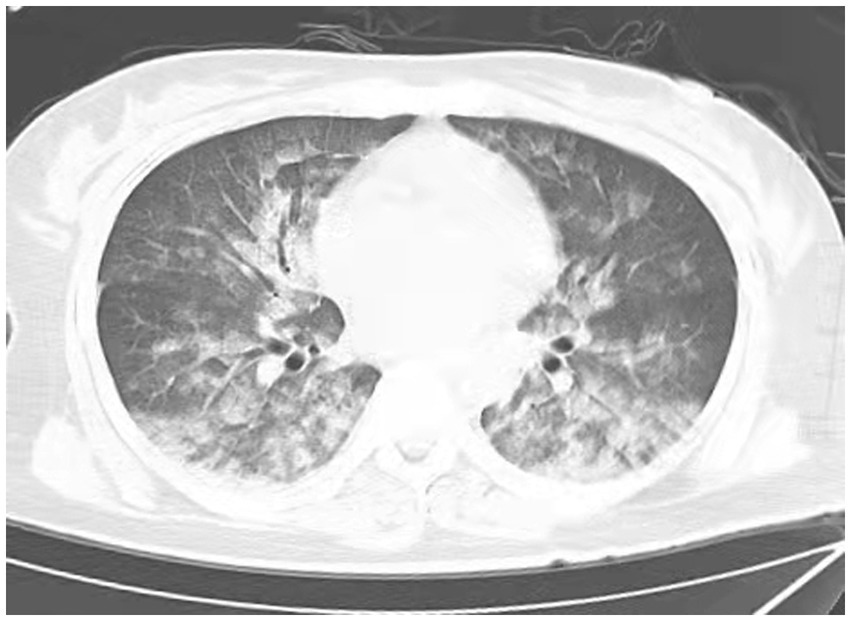

A 38-year-old married female with no previous history of cardiac disease, asthma, pneumonia, or allergies to food or medication presented with a ruptured ectopic pregnancy. On March 9, 2022, at 19:45, she underwent an emergency laparoscopic-assisted salpingectomy under general anesthesia at a local hospital. All preoperative evaluations, including laboratory tests, imaging studies, and physical examinations, were within normal limits. The surgery concluded at 21:00 without complications, and the anesthesia was satisfactory. Intraoperative fluid replacement included 1,000 mL of normal saline. At 21:10, the endotracheal tube was removed, and the patient was alert with no complaints. At 21:15, cardiac monitoring indicated a decrease in peripheral oxygen saturation (SpO2) to approximately 75%. The patient reported chest tightness and dyspnea, with pink frothy sputum. Physical examination revealed clear consciousness, tachypnea, and bilateral pulmonary rales. Immediate oxygen therapy via nasal cannula was started. Arterial blood gas analysis revealed: pH 7.31, partial pressure of arterial oxygen (PaO2) 83 mmHg, partial pressure of arterial carbon dioxide (PaCO2) 47 mmHg. A 12-lead electrocardiogram displayed sinus rhythm without signs of acute ischemia or infarction. After administration of 40 mg methylprednisolone and 20 mg furosemide intravenously, oxygen therapy was switched to a face mask, resulting in a SpO2 of approximately 95%. Due to ongoing chest tightness and dyspnea, the patient was transferred to our emergency department. Upon admission, the patient reported chest tightness and mild dyspnea. Vital signs were: temperature 37.3°C, pulse 100/min, respiratory rate 26/min, blood pressure 108/72 mmHg, SpO2 98% (with face mask oxygen). Physical examination revealed bilateral pulmonary rales, with normal cardiac and abdominal findings and no lower extremity edema. Non-invasive positive pressure ventilation was promptly initiated, along with 20 mg furosemide intravenously. Arterial blood gas analysis showed: pH 7.34, PaO2 127 mmHg, PaCO2 47 mmHg, white blood cell count 16.47*109/l, neutrophil percentage 96.6%, hemoglobin 107 g/L, platelet count 202*109/l, D-Dimmer 1.98 mg/L fibrinogen equivalent units, N-terminal pro-B-type natriuretic peptide 86.5 pg/mL. Chest computed tomography (CT) revealed bilateral pulmonary exudative changes consistent with pulmonary edema (Figure 1). After 6 h, the patient’s symptoms improved, with no dyspnea or chest pain and only a mild cough without sputum. Repeat arterial blood gas analysis showed: pH 7.46, PaO2 285 mmHg, PaCO2 45.9 mmHg. A follow-up chest CT at 12 h demonstrated significant resolution of the bilateral pulmonary exudative changes (Figure 2). Contrast-enhanced CT showed no evidence of pulmonary embolism (Figure 3). The patient’s respiratory status improved over the following days as the pulmonary edema resolved. She was discharged after 6 days without any complaints, and a final chest CT showed no significant abnormalities (Figure 4). A one-month follow-up revealed no residual symptoms.

Figure 1

Chest CT scan depicting increase in diffuse density of the lungs, bilateral ground glass opacities, and dorsal consolidation of lungs because of pulmonary infiltrates, supporting acute pulmonary edema at 0.15 h after extubations. (Extensive, patchy ground-glass opacities and cloud-like shadows were observed in both lungs).